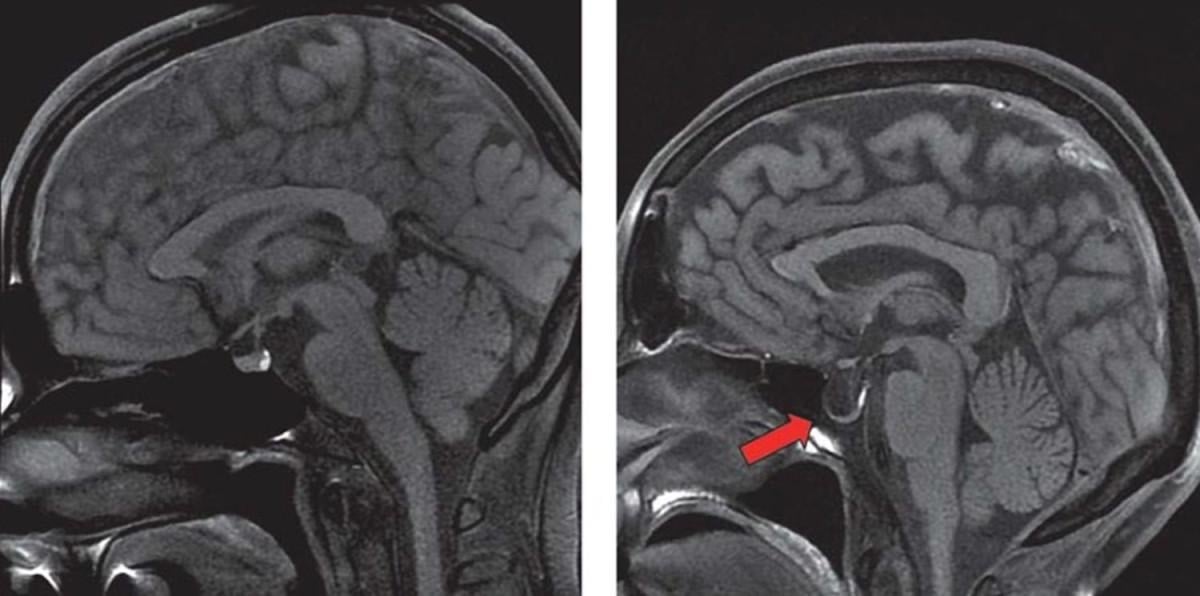

Anatomide "Sella turcica" olarak geçen ve halk arasında "Türk Eyeri" olarak bilinen kemik, vücudun önemli bir yapısıdır.

Bu kemik, kafatasının alt kısmında, gözlerin arkasında yer alır ve şekli, eski Türk atları için kullanılan eyere benzetildiği için bu adla anılır.

Türk eyeri, içinde hipofiz bezini (pituiter bez) barındırır. Hipofiz bezi, hormon üretiminden sorumlu olan ve vücuttaki pek çok önemli işlevi kontrol eden bir bezdir.